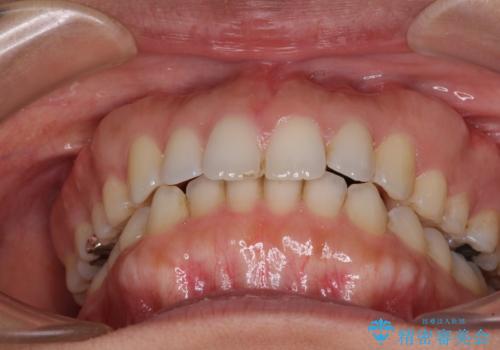

受け口傾向の前歯 すきっ歯の改善

- 前歯の隙間と口元の突出感を気にして来院された患者様です。

嚥下時に舌を突出させる癖があり、成長期に下顎が有意に成長し、歯と歯の間に隙間ができてしまいました。

舌の癖を改善し、インビザラインにて治療を行うこととしました。

舌癖を改善したことで、隙間や突出感を改善することができました。

隙間は後戻りしやすいため、舌側を細いワイヤーで固定することとしました。